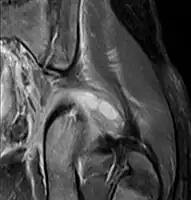

- Coronal fat suppressed post contrast image showing a multiloculated bacterial abscess in the left gluteus minimus muscle due to tropical pyomyositis.